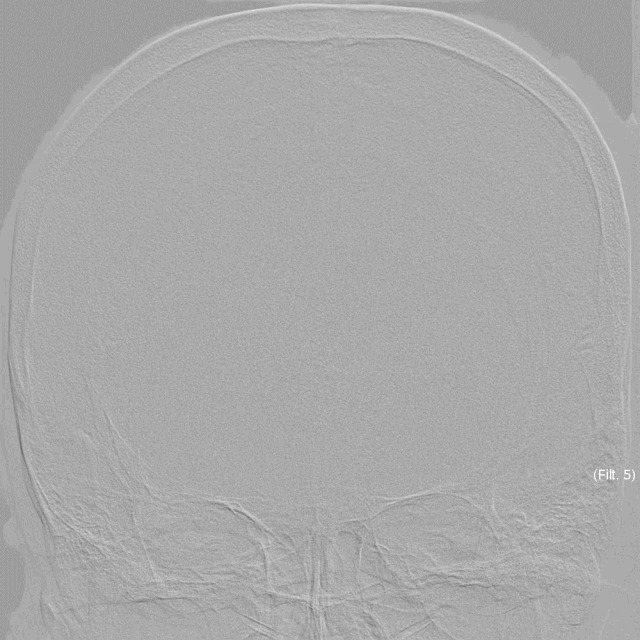

入院后完善全脑血管造影,通过右侧椎动脉造影,我们可以看到基底动脉顶端1枚大型动脉瘤,同侧大脑后动脉、小脑上动脉临近瘤体发出,并且都相对纤细,与基底动脉成角较大。

双侧前循环造影未见明显异常,左侧椎动脉为非优势侧,大脑后动脉与小脑上动脉同样相对纤细。这里我们能够观察到,动脉瘤瘤体内血流相对瘀滞,呈现造影剂滞留的现象。

形态学测量可以看到,本例动脉瘤瘤体较大,右侧大脑后动脉平均直径1mm左右,基底动脉管径2.5mm左右,相差较为悬殊,左侧椎动脉路径迂曲,在治疗上具有一定难度。